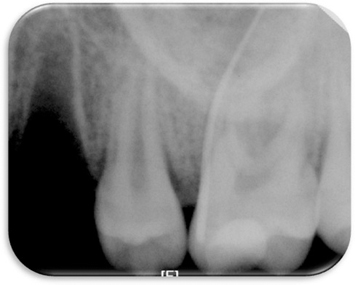

Figure 2

Pre-operative periapical x-ray.

Figure 2 Pre-operative periapical x-ray.